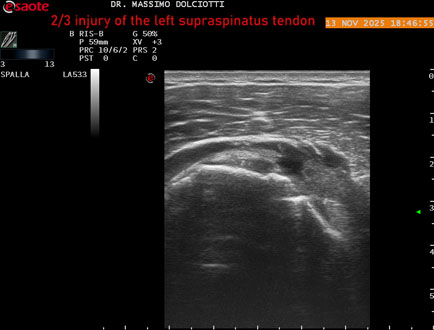

Età Paziente: M 58 anni

Motivazione dell'esame: da 4-5 mesi dolore alla spalla sinistra.

Commento all'esame: le immagini ed il video documentano il tendine sovraspinato sinistro disomogeneo per evidenza, in sede mediale sottobursale, di area ipoecogena di 4,5 mm per uno spessore di 3,3 mm, da ricondurre a lesione parziale che interessa i 2/3 del tendine.

Conclusioni: lesione 2/3 del tendine sovraspinato sinistro (2/3 injury of the left supraspinatus tendon).

Presentazione: Dr. Massimo Dolciotti - Ancona

Elaborazione digitale: Andrea Dini - Ancona